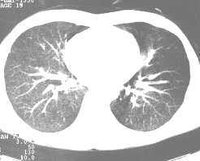

2、影像學檢查胸部X線檢查可以發現肺內病變的部位、範圍,有無空洞或空洞大小,洞壁厚薄等。X線對各類結核病變的透過度不同,通過X線檢查大致能估計結核病灶的病理性質,並能早期發現肺結核,以及判斷病情發展及治療效果,有助於決定治療方案。必須指出,不同病因引起的肺內病變,可能呈現相似的X線影像,故亦不能僅憑X線檢查輕易確定肺結核的診斷。X線攝片結合透視有助於提高診斷的準確性,可發現肋骨、縱隔、膈肌或被心臟遮蓋的細胞病灶,並能觀察心、肺、膈肌的動態。肺結核的X線表現包括:纖維鈣化的硬結病灶,表現為密度較高、邊緣清晰的斑點、條索取或者結節;浸潤性病灶,表現為密度較單,邊緣模糊的雲霧狀陰影;乾酪樣病灶,表現為密度較高,濃淡不一,有環形邊界透光區的空洞等。肺結核病灶通常在肺上部、單側或雙側,促成時間較長,且有多種不同性質的病灶混合存在及肺內播散跡象。凡X線胸片上顯示滲出性或滲出增殖性病灶、乾酪樣肺炎、乾酪樣病灶、空洞(除淨化空洞外),均提示為活動性病變;增殖性病變、纖維包裹緊密的乾酪硬結灶火及纖維鈣化灶等,均屬非活動性病變。活動性病灶的痰中仍可找到結核菌。由於肺結核病變多為混合性,在未達到完全增殖或纖維鈣化時,均仍應考慮為活動性。肺部CT檢查對於發現微小或隱蔽性病變,了解病變範圍及肺病變鑑別等方面均有幫助。

4.x 線胸片兩肺見典型粟粒陰影 。胸CT急性血行播散型肺結核表現為直徑1-3mm大小、密度及分布均勻的粟粒結節;而亞急性和慢性患者表現以上中肺野為主的3-7mm大小、密度及分布不均勻的結節。結節的邊界多數尚清晰,但也有表現邊界模糊;結節隨機分布於肺小葉、小葉間隔及胸膜下。